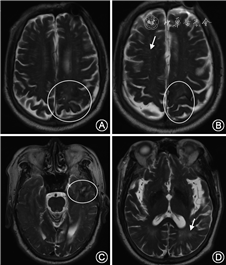

cSS指含铁血黄素在蛛网膜下腔、软脑膜和浅表皮质的沉积,在GRE或SWI序列上呈现沿脑沟分布的线样低信号(图3),有时在T2WI也可看到(图4)。如范围不超过3个脑沟,称为局灶性cSS,3个脑沟以上则称为播散性cSS,推测cSS最可能由cSAH所致[6, 30]。cSS对CAA的诊断具有较高特异度,在病理确诊的一组CAA(多数伴有脑出血)病例中其发生率可达60.5%,在经病理排除CAA的高血压脑出血对照组中则不存在[31]。在另一组pr-CAA病例中,cSS的发生率为40%,而在深部脑出血对照组中小于5%[32]。在鉴别脑出血和常染色体显性遗传脑动脉病伴皮质下梗死和白质脑病(cerebral autosomal dominant arteriopathy with subcortical infarcts and leukoencephalopathy)时,cSS是唯一有价值且对CAA高度特异的影像学标志[33]。在修订的“波士顿诊断标准”中,cSS、脑叶出血和微出血对CAA的诊断被赋予了同等意义[5]。cSS还是预测CAA未来脑出血风险的可靠指标,并且cSS的范围越大,脑出血的风险越高[34, 35, 36]。

CAA患者出现WMH的原因与Aβ沉积导致的血管狭窄、继发缺血和血脑屏障的破坏有关。严重CAA患者WMH负荷重于健康老年人和AD患者。WMH对CAA并没有特异性,但WMH位置分布对其病因有一定提示意义。CAA导致的WMH常见于皮质下,而基底节周围的WMH更多与高血压性小血管病变相关[37, 38]。额叶或前后对称分布的WMH在健康老年人很常见,而后部优势的WMH常见于CAA(图4)[37, 39]。WMH导致不同脑区的连接中断,突出表现为执行功能损害和加工速率下降。CAA中WMH是认知功能损害的独立危险因素。伴随WMH负荷的增加,CAA性脑出血患者基线血肿的体积更大,血肿扩展和出血复发的风险也随之升高[6, 40, 41]。

尽管ICAA与CAA密切相关,但其临床特征显著不同于CAA。ICAA可分为CAA相关炎症(CAA related inflammation, CAA-ri)和Aβ相关血管炎(Aβ related angiitis, ABRA), 两者分别以血管周围炎性浸润和透壁性血管炎为病理特征。ICAA可发生于多个部位,仅有1/3累及枕叶[64, 65]。ICAA症状多样,以亚急性认知功能下降、癫痫和头痛最为常见[66]。ICAA通常为不对称的大片白质病变,影像学特点符合血管源性水肿的特征,可有占位效应、脑实质或脑膜强化(图4),与AD患者接受抗Aβ单克隆抗体治疗后出现的“Aβ相关影像异常(Aβ related imaging abnormality, ARIA)”类似,后者包括大片脑实质水肿、脑沟渗出和脑微出血[16, 65]。ICAA和ARIA可能具有类似的发病机制,针对血管壁内Aβ的免疫反应起到关键作用。在2篇个案报道中,ICAA和ABRA患者的脑脊液中均发现了针对Aβ的抗体[65]。相对于原发中枢神经系统血管炎,ABRA发病年龄相对较大、蛋白升高更为明显、较少发生梗死,出血发生率更高,脑膜强化更为常见,但均不具有特异性[67]。